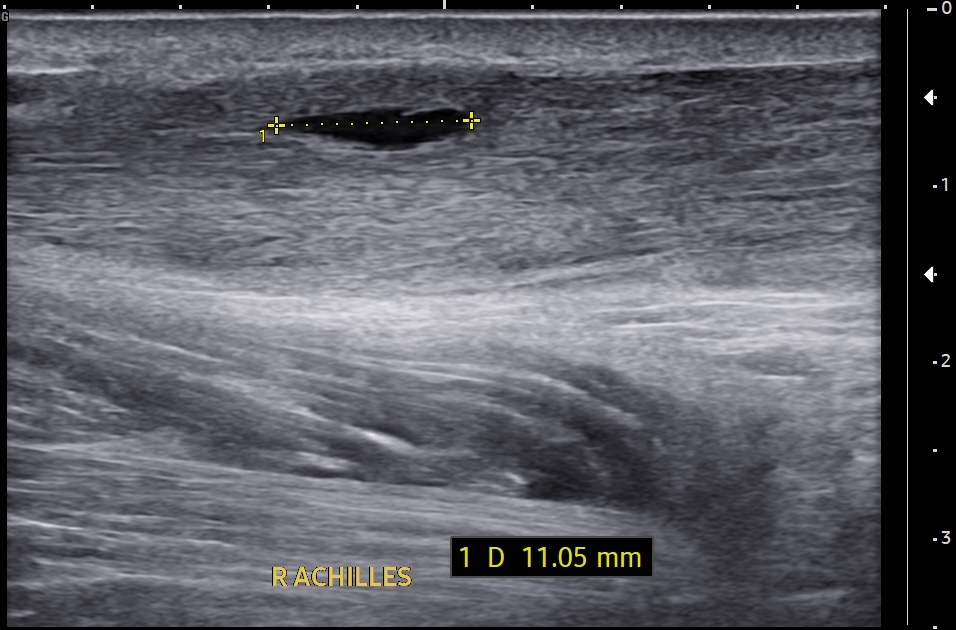

Short-axis ultrasound image of the midportion Achilles tendon showing the tendon thickness measurement.